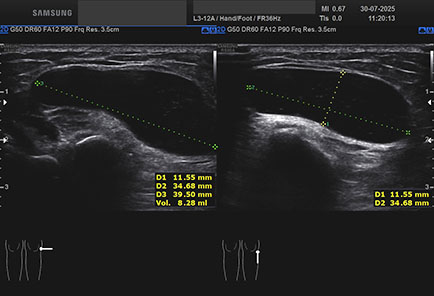

Data inserimento: 15/10/2025

Ecografia del: 30/07/2025

Strumento: Samsung

Sonda: Lineare

Età Paziente: M 70 anni

Commento all'esame: ganglio della articolazione tibio-peroneale prossimale.

Conclusioni: ganglio dell'articolazione tibio-peroneale prossimale (ganglion of the proximal tibiofibular joint).

Realizzazione: Dr. F. Pietro Tarini - Gubbio (PG)